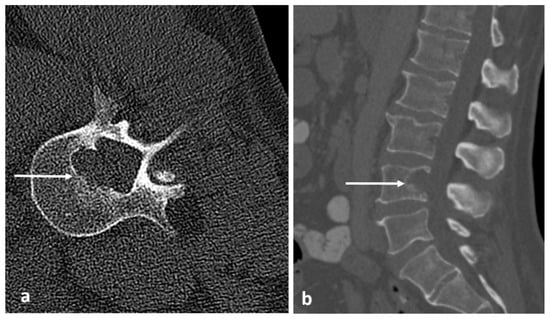

3.2. Osteoid Osteoma

| Osteoid osteoma | Lucent nidus, usually 2–10 mm. May be surrounded by sclerotic rim. | Surrounding marrow oedema on fluid sensitive sequences (best seen on STIR). Nidus can be occult on MRI. |